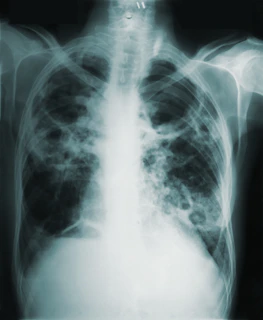

Diagnosis

Diagnosis involves integrating clinical information with imaging and functional testing.

Evaluation commonly includes:

detailed medical and exposure history

physical examination

pulmonary function tests to assess lung capacity and gas exchange

high-resolution computed tomography of the chest

blood tests to identify autoimmune or inflammatory causes

In some cases, a lung biopsy may be necessary to confirm the diagnosis and determine the specific pattern of lung injury.